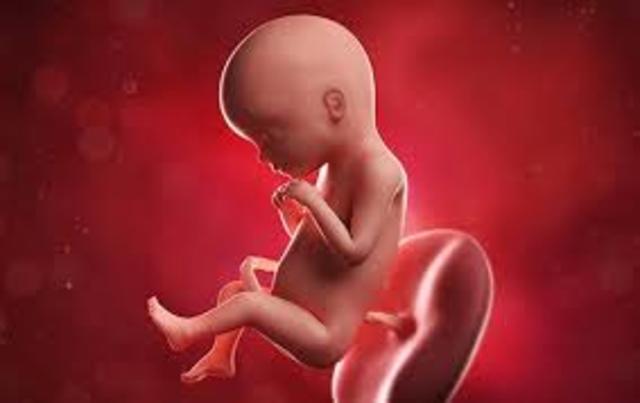

SEMANA 30

Su cerebro ha crecido y se acomoda al tamaño de su cabeza, sus pulmones continúan madurando, comienza a buscar la posición definitiva que tendrá al nacer.